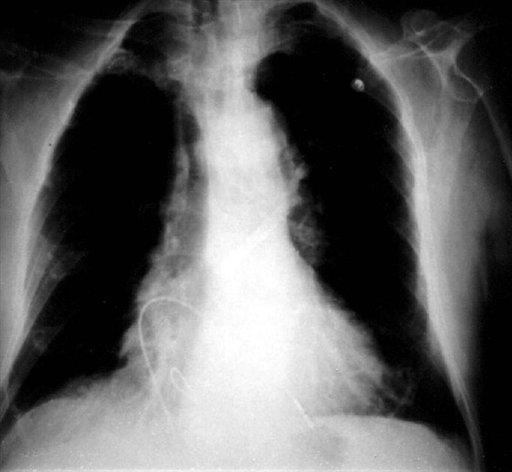

Ingeniero colombiano crea un marcapasos del tamaño de un tercio de un grano de arroz

Bogotá, 21 ago (EFE).- El ingeniero electrónico colombiano Jorge Reynolds, creador del primer marcapasos hace 53 años, anunció este fin de semana el lanzamiento de un dispositivo tan grande como un tercio de un grano de...